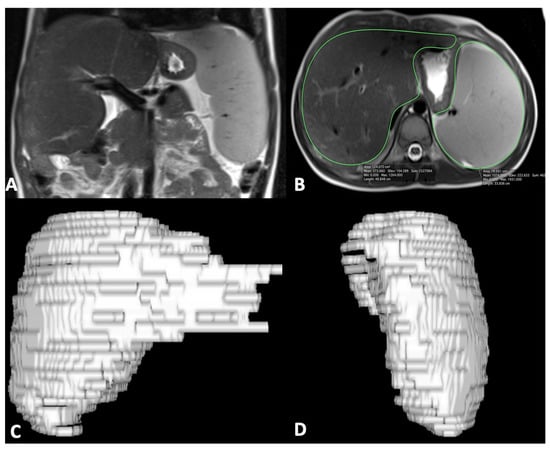

2.3. US and MR Imaging Acquisition and Processing

- Caruso, M.; Cuocolo, R.; Di Dato, F.; Mollica, C.; Vallone, G.; Romeo, V.; Petretta, M.; Liuzzi, R.; Mainenti, P.P.; Iorio, R.; et al. Ultrasound, shear-wave elastography, and magnetic resonance imaging in native liver survivor patients with biliary atresia after Kasai portoenterostomy: Correlation with medical outcome after treatment. Acta Radiol. 2020, 61, 1300–1308. [Google Scholar] [CrossRef]

- Caruso, M.; Di Dato, F.; Mollica, C.; Vallone, G.; Romeo, V.; Liuzzi, R.; Mainenti, P.P.; Petretta, M.; Iorio, R.; Brunetti, A.; et al. Imaging prediction with ultrasound and MRI of long-term medical outcome in native liver survivor patients with biliary atresia after kasai portoenterostomy: A pilot study. Abdom. Radiol. 2021, 46, 2595–2603. [Google Scholar] [CrossRef]

- Van Der Vorst, J.R.; Van Dam, R.M.; Van Stiphout, R.S.A.; Van Den Broek, M.A.; Hollander, I.H.; Kessels, A.G.H.; Dejong, C.H.C. Virtual Liver Resection and Volumetric Analysis of the Future Liver Remnant using Open Source Image Processing Software. World J. Surg. 2010, 34, 2426–2433. [Google Scholar] [CrossRef] [PubMed] [Green Version]